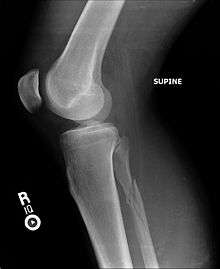

Posterior malleolus fracture

Upper fibula fracture